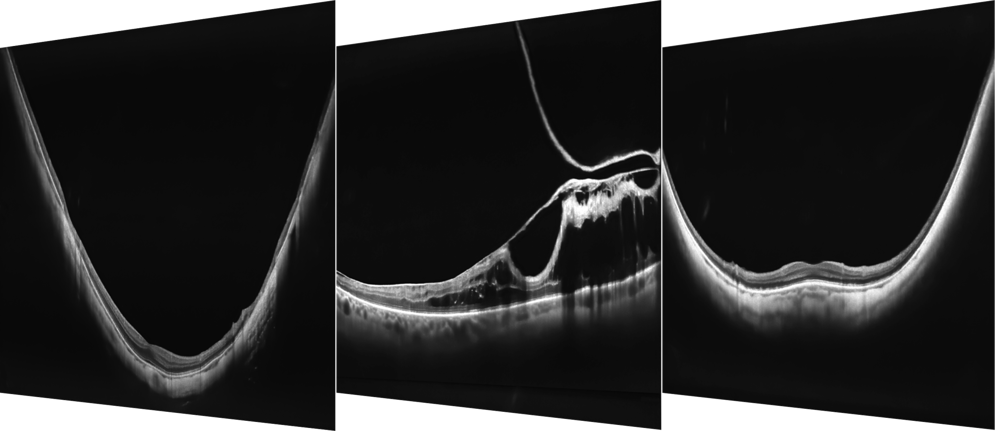

LE NOUVEAU LOGICIEL EXTENDED DEPTH ET LES CAPTURES FULL RANGE

Avec des scans présentant le nouveau logiciel Extended Depth, basé sur notre technologie Full Range, fournit des scans d'une profondeur accrue pour une observation fiable et pratique des cas difficiles. Avec des scans présentant une profondeur étendue, ce nouveau mode d'imagerie est parfait pour diagnostiquer même les patients très myopes.

- Analyse Chambre Antérieure.